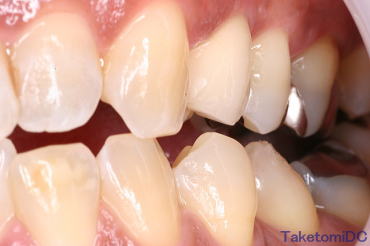

セラミックの症例です

セラミックの歯をかぶせた方の症例です。どの歯がかぶせものだか分かりますか?歯茎との色調も合っているので簡単にはどれがかぶせものだか分からないのではないでしょうか。

マウスを画像に乗せると答えが出ますよ |